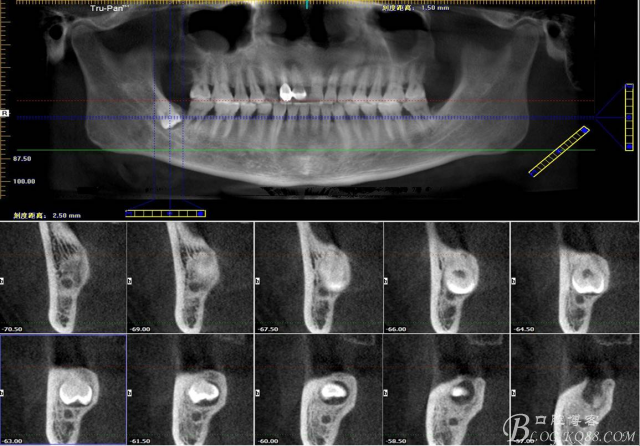

一、術(shù)前全景片影像:

二、術(shù)前CBCT影像:

圖1. 47牙冠的近中面緊鄰下頜神經(jīng)管

圖2.判斷47牙根是否吸收

圖3.通過(guò)矢狀面和冠狀面來(lái)判斷48與下頜管及47的關(guān)系